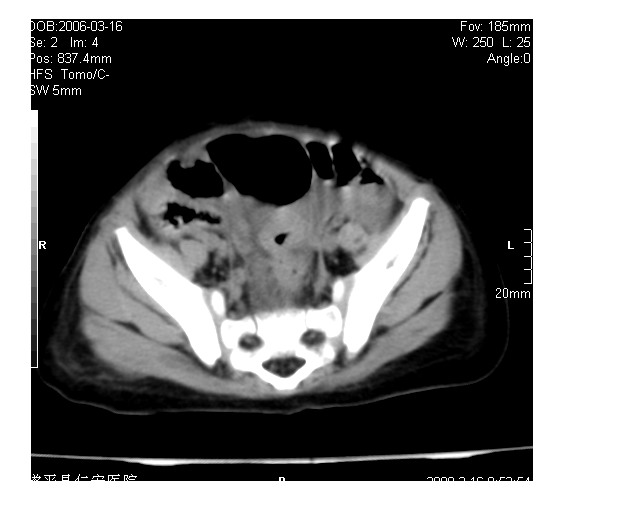

以下是引用lkc8963在2008-3-16 12:49:00的发言:[br]盆底巨大混杂密度肿块,富含多种组织成分包括脂肪/液体/软组织/钙化,边界清楚,向前压迫肠管及膀胱,向后突入骶尾部皮下脂肪层,首先考虑畸胎瘤,诊断时需要与脊柱裂/囊性淋巴管瘤等区别。